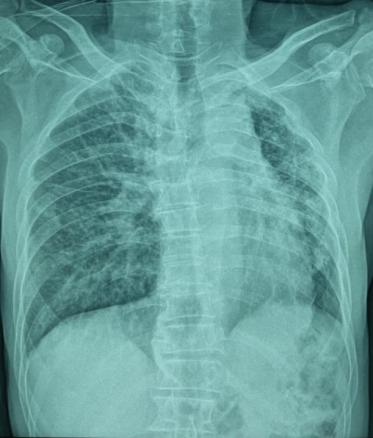

Un homme âgé de 66 ans, sans antécédents particuliers, est admis aux urgences pour la prise en charge d’un traumatisme thoracique minime. Une radiographie thoracique montre une asymétrie de taille des deux champs pulmonaires avec une déviation médiastinale vers la gauche (fig. 1). Un angioscanner thoracique montre une agénésie de l’artère pulmonaire gauche, une hypoplasie du poumon homolatéral et des lacérations vasculaires systémiques d’origine bronchique vascularisant le poumon gauche (fig. 2).

Le diagnostic repose classiquement sur l’angiographie, mais l’angioscanner reste l’examen de référence  : il montre l’absence de structure vasculaire sur le trajet de l’artère pulmonaire, avec une paroi lisse et régulière entre l’artère pulmonaire primitive et l’artère pulmonaire droite ou gauche résiduelle, et permet également d’objectiver une éventuelle hypoplasie associée.5